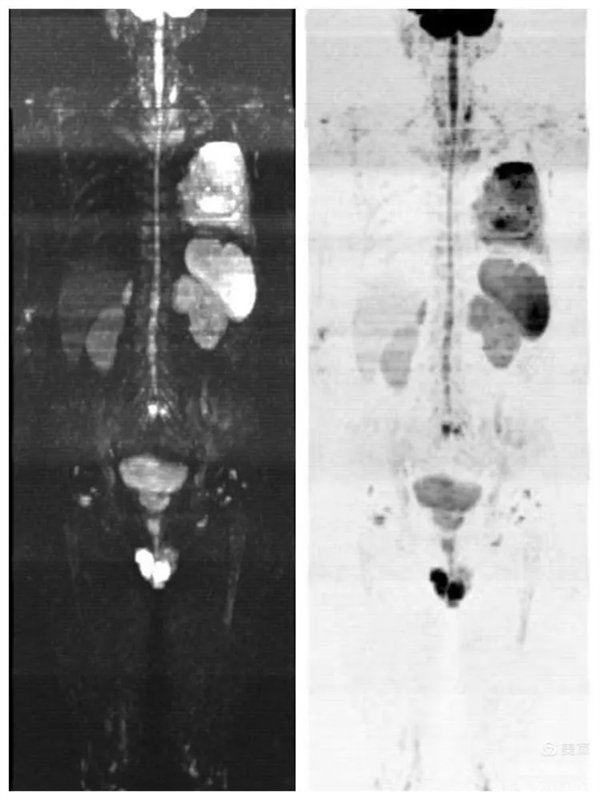

患者,男,左肺病变,为了查找全身有无其它病灶,明确分期,制定最合适的诊疗方案,临床医生决定行“类PET”即全身磁共振弥散成像(WB-DWI)检查。

图1:全身弥散成像图像

图2:全身弥散成像反转图

磁共振全身弥散加权成像(WB-DWI),是将弥散加权成像技术与自动拼接技术和全景成像矩阵相结合而获得全身的弥散加权成像影像。所得影像经黑白翻转后可达到与正电子发射计算机体层显像(PET)影像类似的效果,故被称为“类PET”,是近年来发展起来的全新影像检查新技术。

该技术能够进行全身大范围扫描,并加以3D后处理重建,可获得全身肿瘤筛查、良恶性肿瘤的鉴别、肿瘤TNM分期及疗效随诊等诊断信息,全身弥散技术把肌肉、脂肪、肝脏等组织背景信号抑制掉,突出了病变的显示,大大提高了病变组织尤其是恶性肿瘤及其转移灶的检出率。